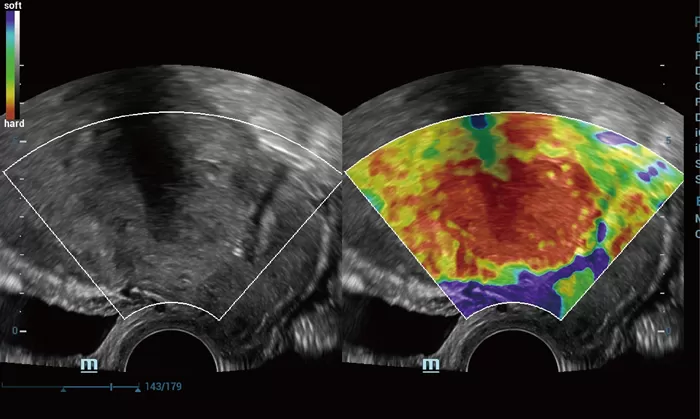

The Resona series, stands out not only for its cutting edge imaging technology but also for its flexible analysis tools offering high display quality and increased diagnostic precision.

The innovative technologies:

- New iLive with Hyaline

- Dynamic Focusing